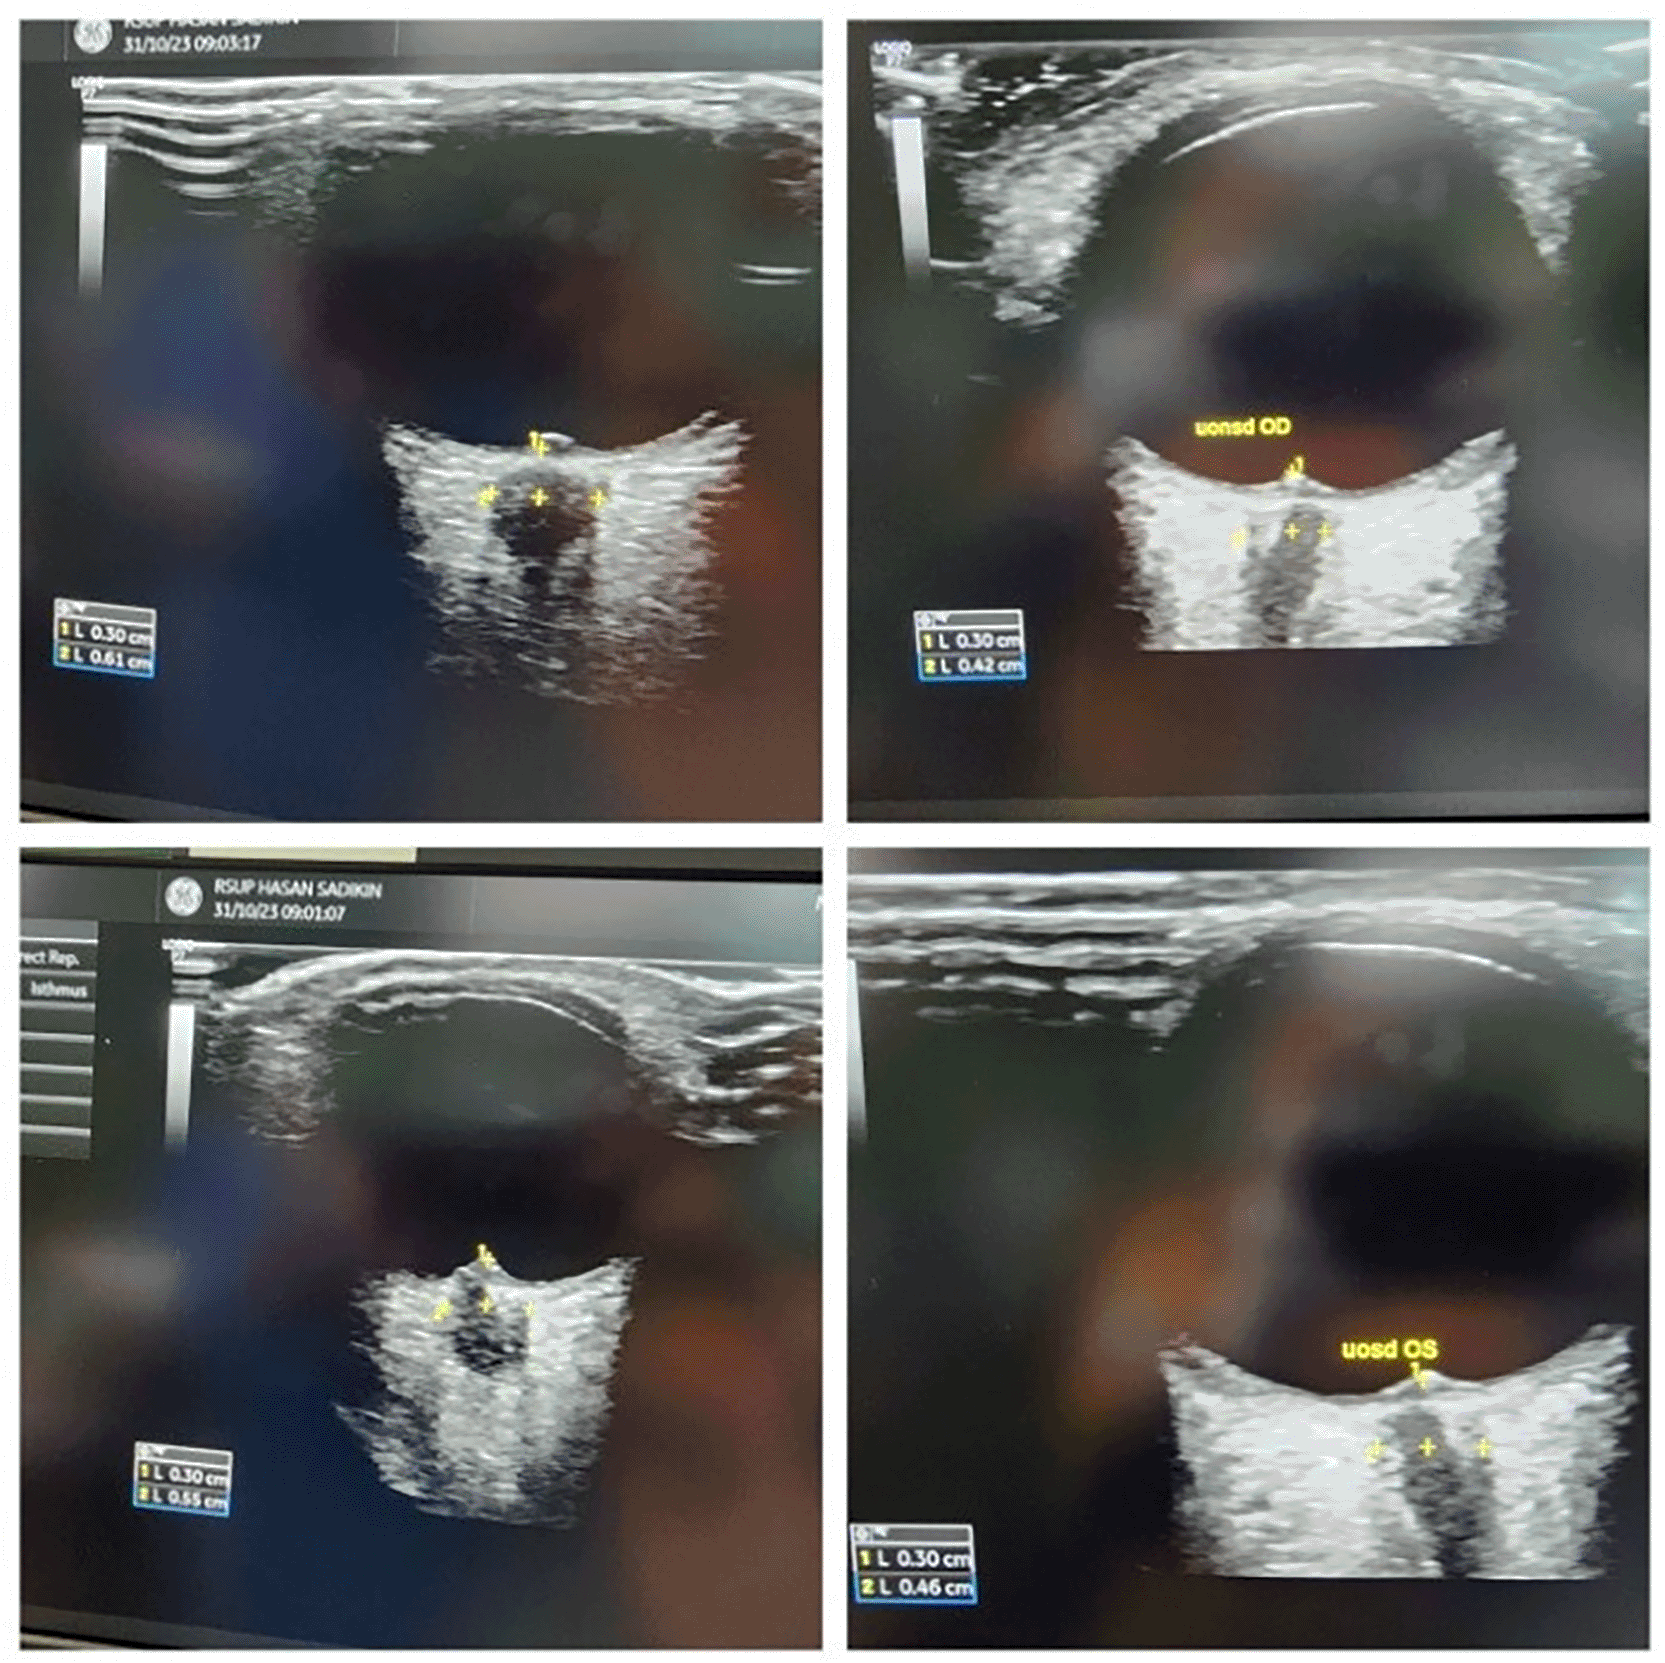

Perioperative ICP was monitored via bedside ultrasound using optic nerve sheath diameter (ONSD) and transcranial Doppler (TCD). Baseline ONSD values were elevated (OD: 0.62 mm, OS: 0.55 mm), and TCD showed high pulsatility index (PI of MCA) values 1.73 on the right (~ ICP 17.63) and 2.02 on the left (~ ICP 20.79). After induction and magnesium infusion, ONSD decreased (OD: 0.42 mm, OS: 0.46 mm), and PI improved (right: 1.2; left: 1.4), reflecting reduced ICP and improved cerebral compliance ( Table 2).

Real-time ultrasound monitoring of ICP was performed using optic nerve sheath diameter (ONSD) and transcranial Doppler (TCD). Initial ONSD values were elevated (OD 0.62 mm; OS 0.55 mm), and pulsatility indices from the middle cerebral arteries indicated raised ICP (PI: right 1.73; left 2.02). Post-MgSO4 administration, ONSD decreased (OD 0.42 mm; OS 0.46 mm), and PI improved.

Bedside ultrasound monitoring of optic nerve sheath diameter trends has been validated as a reliable non-invasive surrogate for intracranial compliance in pediatric populations, particularly in neurosurgical and neurocritical care pathways. Representative pre- and post-induction optic nerve sheath diameter measurements illustrating directional change rather than absolute ICP quantification are shown in Figure 1. Directional reduction of pre-induction elevated ONSD values (from 0.62 mm right; 0.55 mm left to <0.5 mm range post-induction) adds physiologic coherence to suspected ICP improvement and supports individualized intraoperative titration logic, especially when interpreted as trend-based compliance directionality rather than absolute numeric diagnosis.16,17 Transcranial Doppler assessment of middle cerebral artery pulsatility indices is a validated method for reflecting changes in cerebral compliance and perfusion directionality in children, including in traumatic and neurocritical populations. Corresponding changes in middle cerebral artery flow dynamics assessed by transcranial Doppler are illustrated in Figure 2. The observed reduction from pre-induction elevated PI (2.02; 1.73) into improved ranges (1.2; 1.4) remains consistent with literature-mapped pediatric Doppler–compliance trending, reinforcing physiologic plausibility without making overstatements that transcend case-level inference.16,18,19